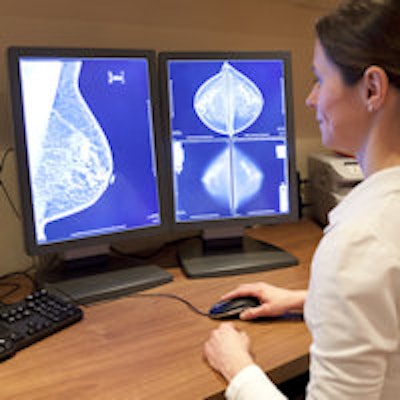

The finding is discouraging in light of the fact that annual mammography screening has been shown to reduce breast cancer death by 19%, according to a team led by Dr. Susan Harvey, director of breast imaging at Johns Hopkins. Harvey's group conducted a survey that assessed women's knowledge of mammography's benefits and its coverage status under the Patient Protection and Affordable Care Act (ACA), as well as obstacles to it.

Seventy-eight percent of survey respondents agreed that mammography screening is important, but only 54% reported having an annual exam, the researchers found. Women with health insurance were two times more likely than those without to have annual mammography (57% versus 23%). In fact, 30% of uninsured women reported never having had a mammogram, compared with 10% of insured women.

Almost half of the women who participated in the survey experienced being called back after an inconclusive mammogram; 89% of these recalls proved to be benign. Harvey's group found a marked emotional effect on women who were called back, especially those between the ages of 40 and 50: In this age group, 58% reported being scared and 57% reported being stressed by being recalled for more testing.

Also, recalls are expensive, Harvey and colleagues noted. In 2010, the cost of callbacks in the U.S. was $1.6 billion. And the U.S. rate of recalls after inconclusive mammograms tends to be high -- more than double the rate in the U.K., for example.

"When we did our literature search, we were finding estimated U.S. recall rates as high as 15% -- and the guideline is 10% or less," Harvey told AuntMinnie.com. "Personally, I think 10% is too high. And as breast imagers we may think that it's 'just a recall,' but that's not how women feel. They're really frightened."

Johns Hopkins has reduced its own recall rate by gathering and evaluating recall data, re-examining callback cases, and determining the outcome of the recall. Finally, Johns Hopkins requires that two breast imagers must agree that a recall is necessary before it is made, according to Harvey.

"When we started this process, our group recall rate was around 11%," she said. "Now it's half that. Our goal is 5%, so we're getting close."